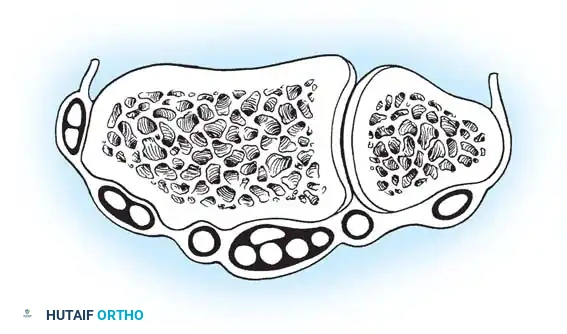

A profound understanding of the dorsal extensor compartments and the underlying capsuloligamentous structures is non-negotiable for safe portal placement. The radiocarpal joint is a complex, multi-axial articulation. The distal radius possesses a normal volar tilt of 11 to 12 degrees and a radial inclination of 22 degrees. This osseous geometry dictates the trajectory of instrument insertion; all radiocarpal portals must be established with a corresponding 10 to 15-degree volar and proximal angulation to avoid iatrogenic scuffing of the articular cartilage.

PORTAL ANATOMY AND PLACEMENT

Wrist arthroscopy portals are anatomically defined by their relationship to the six dorsal extensor compartments. Precise portal placement is critical to avoid injury to cutaneous nerves, extensor tendons, and articular cartilage.

The midcarpal joint is a separate synovial cavity and must be evaluated independently to assess the distal aspects of the SL and LT ligaments and the capitohamate articulation.

* Midcarpal Radial (MCR) Portal: Located approximately 1 cm distal to the 3-4 portal, in a palpable soft depression between the capitate, scaphoid, and lunate. It is in line with the radial border of the third metacarpal.

* Midcarpal Ulnar (MCU) Portal: Located approximately 1 cm distal to the 4-5 portal, aligned with the axis of the fourth metacarpal, providing access to the triquetrohamate and lunotriquetral articulations.